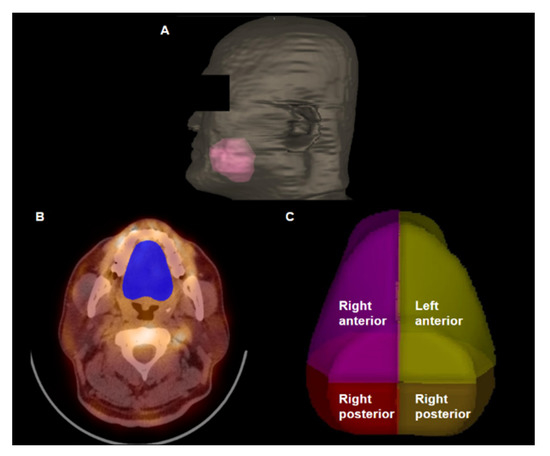

2. Case Presentation